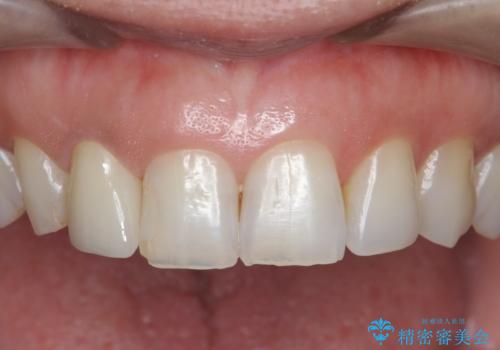

- 16万円(仮歯・ファイバーコア・ジルコニアクラウンスペシャル)費用は治療当時の料金となります

セラミック治療を行う前にきっちりと根管治療を行うことが長期的に持つ可能性を高めます。